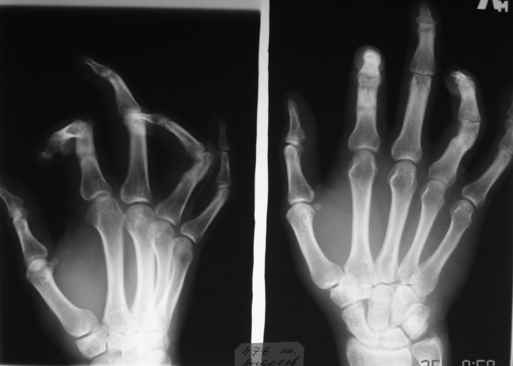

Обратился больной с контрактурой 2-4 пальцев кисти. Травма год назад - рука попала в шнек. Планируется оперативное лечение. Имеет-ли кто опыт укорачивающих остеотомий фаланг пальцев в подобных случаях?